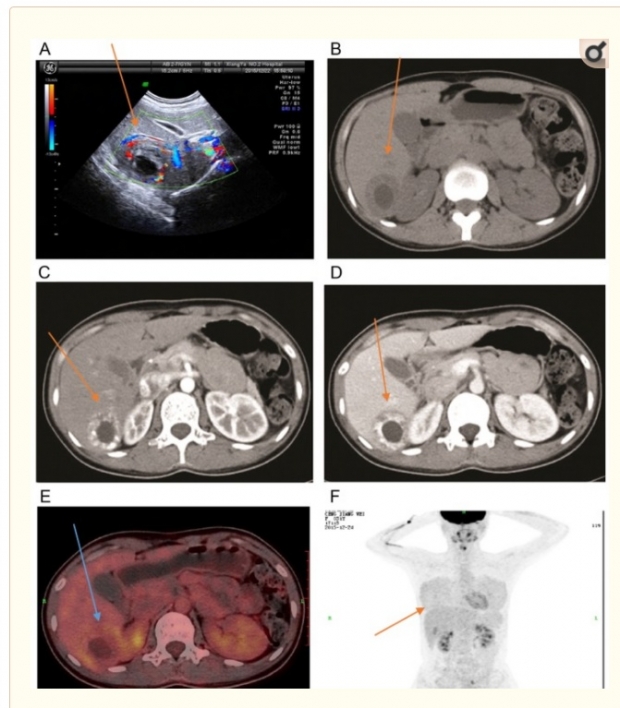

캐나다의 소아과 의사인 마이클 나비는 14일(현지시간) SNS를 통해 33세 여성 환자의 사례를 공개했다. 공개된 글에 따르면 33세 여성 환자는 월경이 2주간 이어진 비정상적인 출혈이후 병원을 방문해 초음파 검사를 받았다.

현지 의료진은 복부 전반을 대상으로 초음파 검진을 실시하던 중 간에서 특이사항을 발견했고, 분석 결과 간에서 태아가 자라는 자궁외 임신이라는 사실을 확인했다.

이를 확인한 현지 의료진은 “이 환자의 경우 수정란이 간까지 이동한 뒤 간에서 착상된 것으로 보인다. 환자는 자궁 외 임신이 확인되기 전 약 한달 동안 복부 팽만감의 증상을 겪었다”고 설명했다.

이 여성은 2008년 제왕절개 수술을 받은 이력 외에는 별다른 병력이 없었고, 6년간 사용해 온 삽입형 피임기구도 정상 위치에 있었으나 자궁 외 임신이 된 것으로 확인됐다. 당시 의료진은 수정란이 간에 착상된 것을 확인한 뒤 곧바로 수술을 받고 건강을 회복했다.

이어 “간 임신은 임신 초기에 진단되지 않는 경우가 많아 최적의 치료시기를 놓치기도 한다. 대부분의 간 임신 환자는 간이 파열된 뒤 수술을 위해 입원하는 경우”라면서 “종합적인 검사는 희귀 자궁 외 임신 환자에게 적절한 치료를 적시에 할 수 있는 귀중한 시간을 확보하는 역할을 할 것”이라고 덧붙였다.